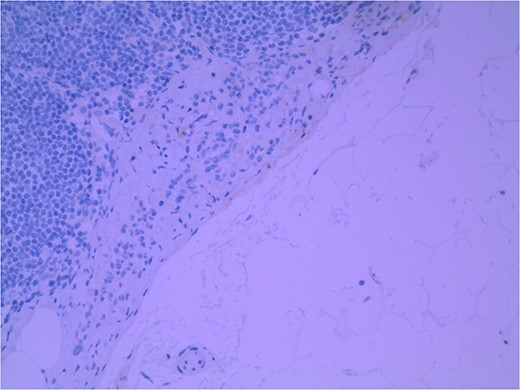

Lymph node specimens were sent for haematoxylin and eosin (H&E) staining (Fig. 3) and IHC analysis. The sections showed mild reactive changes and benign intracapsular nevoid rests. IHC analysis showed that these cells were negative for HMB-45 (Fig. 4) and were positive for both Sox10 and p16 (Figs 5 and 6). Consensus at the Multidisciplinary Team Meeting was that the appearance was in keeping with benign naevoid rests as opposed to melanoma deposits, given the location of the cells, morphology and immunohistochemistry. Surveillance was recommended.

Lymph node with IHC using p16 stain, staining nevoid melanocytes; × 100 magnification.

Several IHC stains are in use in the pathological interpretation of primary lesions and SLN biopsies. The antibody HMB-45 reacts with most melanomas. In a primary lesion, HMB-45 is immunoreactive with intraepidermal and superficial dermal components of benign nevi [14]. In a lymph node, however, benign nevoid cells are negative for HMB-45 and appear bland. A loss of HMB-45 expression has been reported in 20% of melanocytic metastasis, illustrating the need for further diagnostic testing [14]. Sox10 is a nuclear transcription factor that stains benign and malignant melanocytic cells. It indicates the extent of melanocytic spread but does not differentiate between benign nevi and metastatic melanoma [15]. Immunostaining for the tumour suppressor gene p16 differentiates between benign naevi and melanocytic metastases in the SLN. One study demonstrated positive nuclear and cytoplasmic p16 staining in all nevi (dermal and lymph node) and the absence of nuclear p16 staining in all but one melanoma metastasis [14]. No single stain is completely sensitive for melanocytic metastases, and a confident diagnosis relies upon cell location, morphology and multiple IHC techniques. SLN biopsy in the current patient demonstrated intracapsular melanocytic cells which stained negative for HMB-45, and positive for Sox10 and p16, in keeping with benign nevoid rests as opposed to metastatic melanoma.